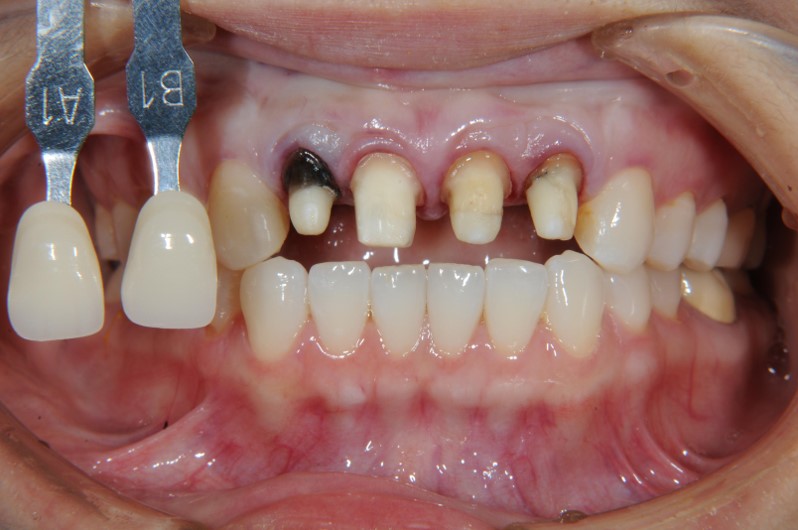

上顎前牙有瘻管,牙齒變色,右下有阻生齒與蛀牙

治療前,牙齦旁有黑邊

美白前,牙齒預比色-B3

印模,比色